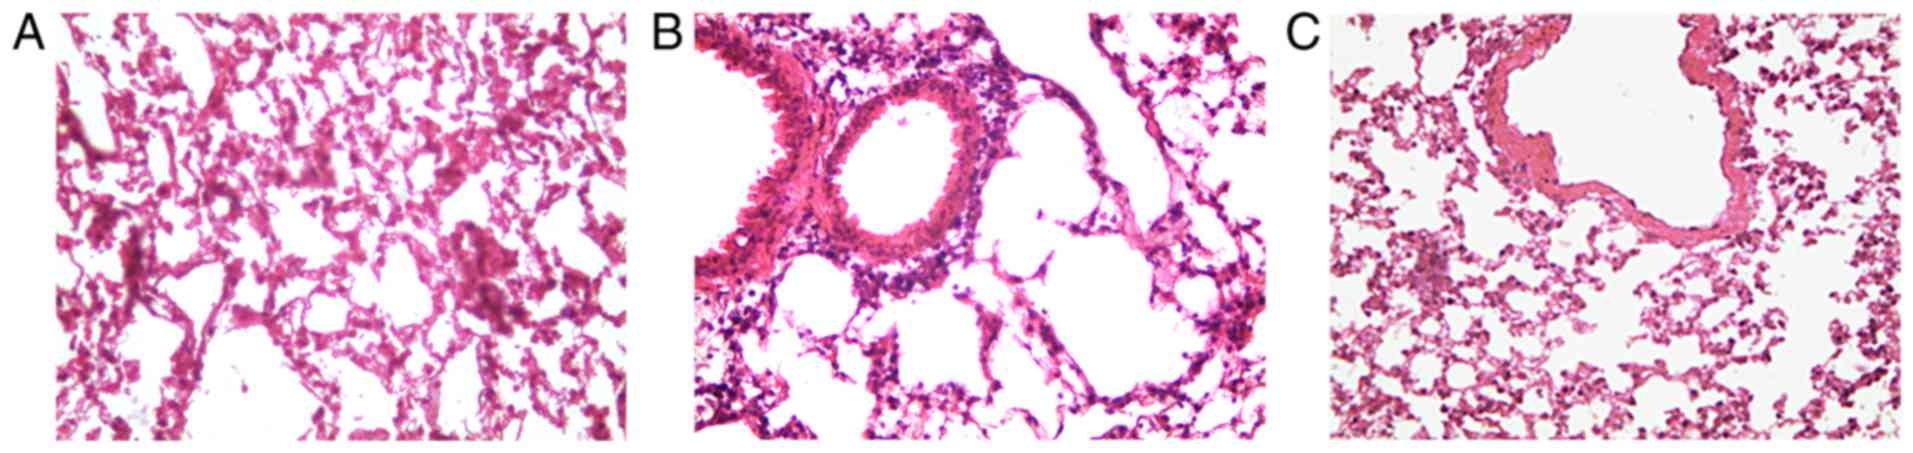

After the last challenge, the right lungs were removed from the chest cavity and immersed in 10% neutral buffered formalin at 25°C for 24 h. Lung samples were then embedded in paraffin and sectioned by using a microtome (5-µm). After dewaxing in xylene, rehydrating in graded ethanol, the sections were stained with haematoxylin at 25°C for 3 min and eosin at 25°C for 30 sec to assess the infiltration of inflammatory cells. All images were assessed at a magnification of ×20.

The murine model of airway inflammation was established through repetitive OVA sensitization. Thereby, an asthmatic phenotype similar to that observed in human asthma was established. Histological analysis of H&E-stained lung tissue indicated that OVA induced inflammatory cell infiltration and pathological transformation in the lung tissues. However, treatment of OVA-challenged mice with ML-7 significantly alleviated the degree of tissue inflammation and infiltration. Furthermore, the pathological changes were milder (Fig. 1). The serum levels of OVA-s IgE in the OVA group were significantly higher compared with those in the control group (131.46±10.72 vs. 25.37±4.89 ng/ml; P=0.004; Fig. 2A). Based on the histological and serological analysis, it was determined that the model was successfully established. The total number of inflammatory cells, including neutrophils, eosinophils, macrophages and lymphocytes in the BALF, are hallmarks of inflammation in the mice at the cellular level. Particularly eosinophils are generally considered the hallmark of the onset of asthma. Compared with the control group, the total number of cells and eosinophils increased in the OVA group (P<0.001 for each comparison; Fig. 2B and C). Of note, the percentage of eosinophils in the OVA+ML-7 group was significantly decreased compared with that in the OVA group (0.012±0.007 vs. 0.068±0.01; P=0.0075; Fig. 2C). The total number of cells and the percentage of neutrophils in the OVA + ML-7 group was also decreased compared with that in the OVA group (Fig. 2B and D). This partly reflected that ML-7 inhibited the accumulation of eosinophils in asthma-like airway inflammation.